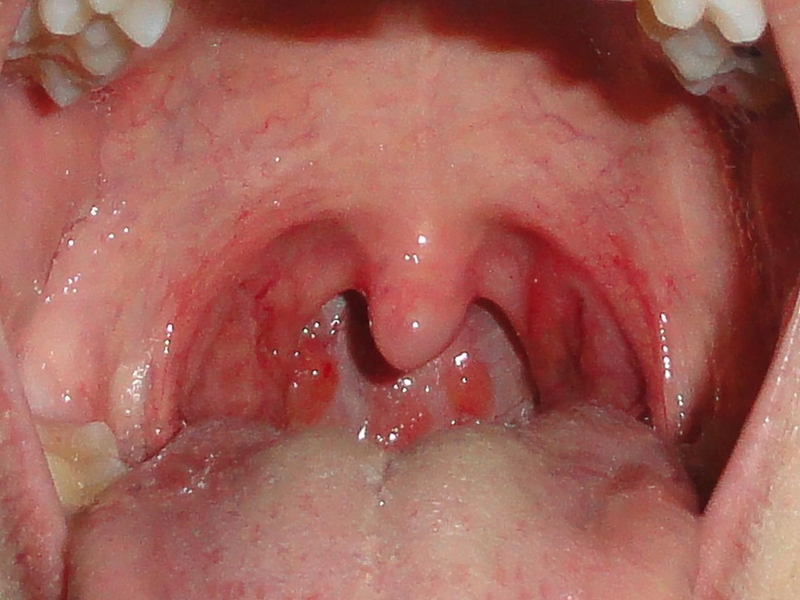

Những triệu chứng viêm amidan mãn tính là gì?

Các triệu chứng viêm amidan mãn tính phổ biến là:

• Đau họng

• Amidan phì đại

• Các hạch cổ sưng to và đau

• Chứng hôi miệng

Đừng bỏ qua các triệu chứng viêm amidan mãn tính 2Đặc điểm cấu tạo của amidan có nhiều khe hốc nên đây chính là những nơi cư trú lý tưởng cho các mầm bệnh phát triển